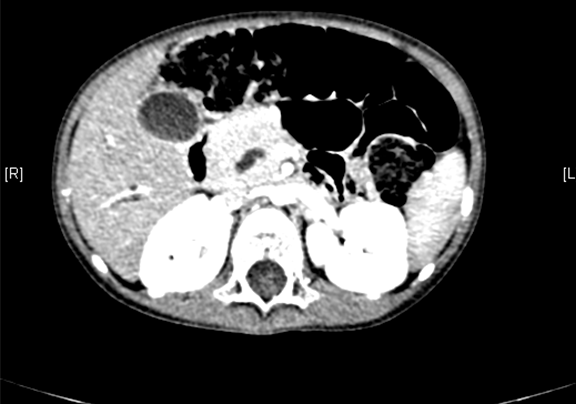

上腹部增强CT:肝内外胆管扩张,考虑先天性胆管扩张症可能性大。

术前CT检查:

动脉期